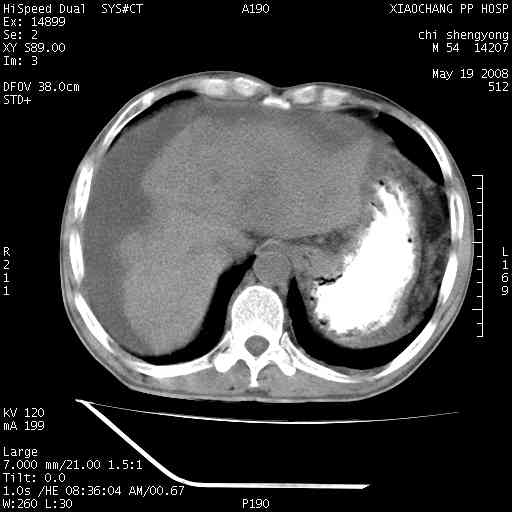

以下是引用zjzjr在2008-5-21 10:52:00的发言:[br]肝左叶巨块型肝癌伴门静脉左支瘤栓形成.肝硬化、腹水,胃底静脉曲张,脾术后改变。

以下是引用随光逐影在2008-5-21 16:20:00的发言:[br]1)肝左叶肝癌伴门静脉左支瘤栓形成,腹膜后淋巴结转移。2)肝硬化、腹水、胃底静脉曲张。3)胆囊炎。4)脾脏缺如,为切除术后所致。